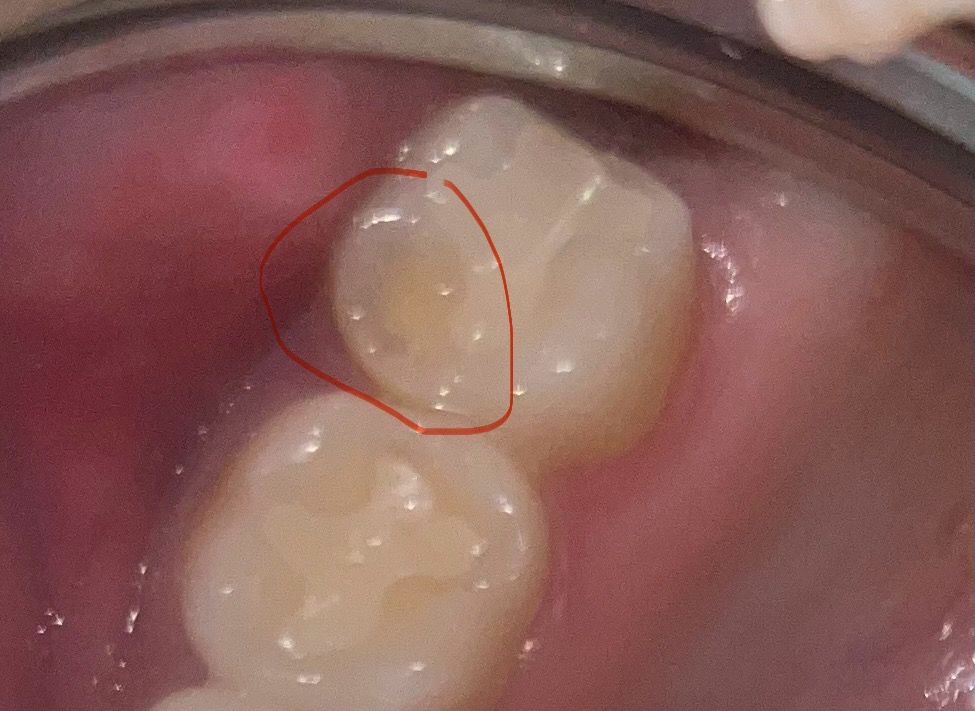

치아 마모인가요 아님 교합조정 때문에 깎은 건가요?

최근 거울로 상악 어금니를 보니 저렇게 움푹 들어가있어요. 5년전에 인레이 치료를 받앗는데 보통 교합점 맞춘다고 살짝 가는 것은 알고 있지만 저렇게 까지 확 깎아져있어서 뭔가 싶어요. 교합때문에 저렇게까지 깎나 해서요.그래서 저 부분은 하악 어금니와 아예 닿지 않아요.

이상한 점은 맨 끝 어금니 4개 다 인레이 했고 다른 이들은 사진 속 26번과 비슷하게 되어있어요. 아래 어금니와도 잘 맞닿구요. 노란색이 상아질이라고 알고있는데 걱정됩니다.

1. 교모 마모에 의한 것인지

2. 교합조정때문에 갈아둔 것인지.

3. 교합 조정을 저렇게까지 많이 깎나요?

4. 마모에 의한것이라면 심한정도인지, 저부분을 레진 올릴수 있는지

상악의 어금니 바깥쪽은 비기능교두로 위아래 어금니가 물릴때 안닿습니다

교합조정시 건드릴 필요가 없고 마모가 잘 되는 곳도 아닙니다

저곳이 마모가 된다는 건 이갈이나 이악물기 습관이 있을지 의심되는 부분입니다